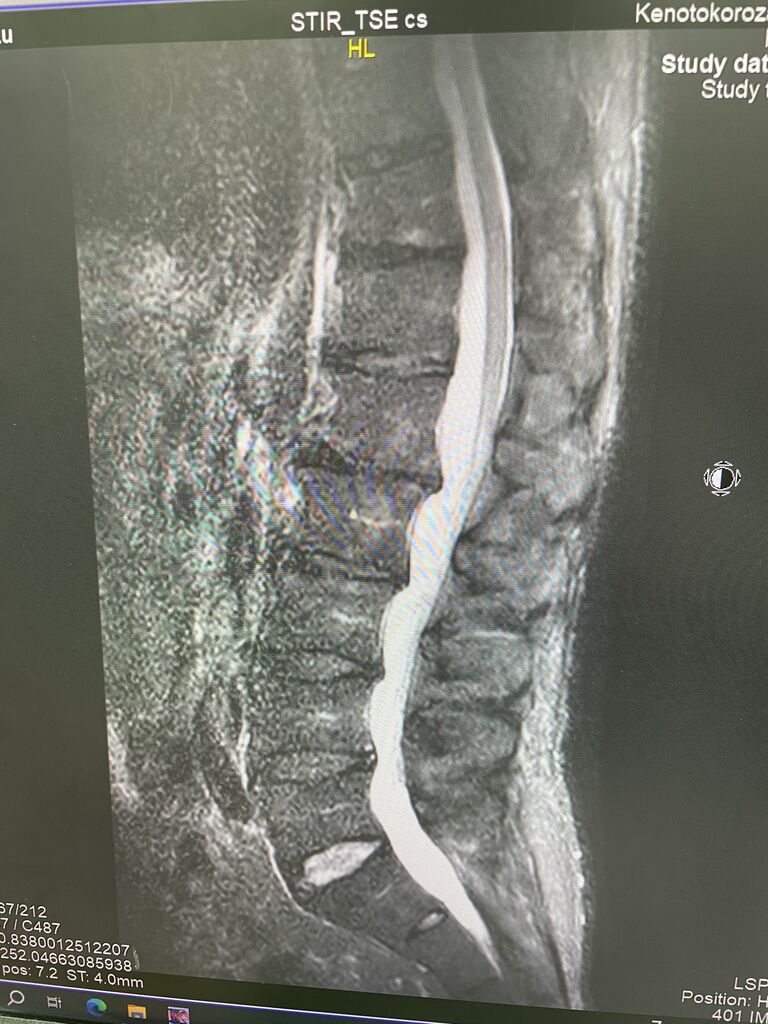

MRIの研修会です

最近、脊柱管狭窄症の患者様が増えて参りましたので

MRIの読影をしながら、椎間板の動きの

研修です^_^

腰の痛みが続き、MRIにて、

脊柱管狭窄症がありますが、

L5 /S1の椎間板だけ、正常な特殊な腰でした、

ストレッチ、筋肉トレーニング、

立体動態波、微弱電流で

良くなっていくと思います